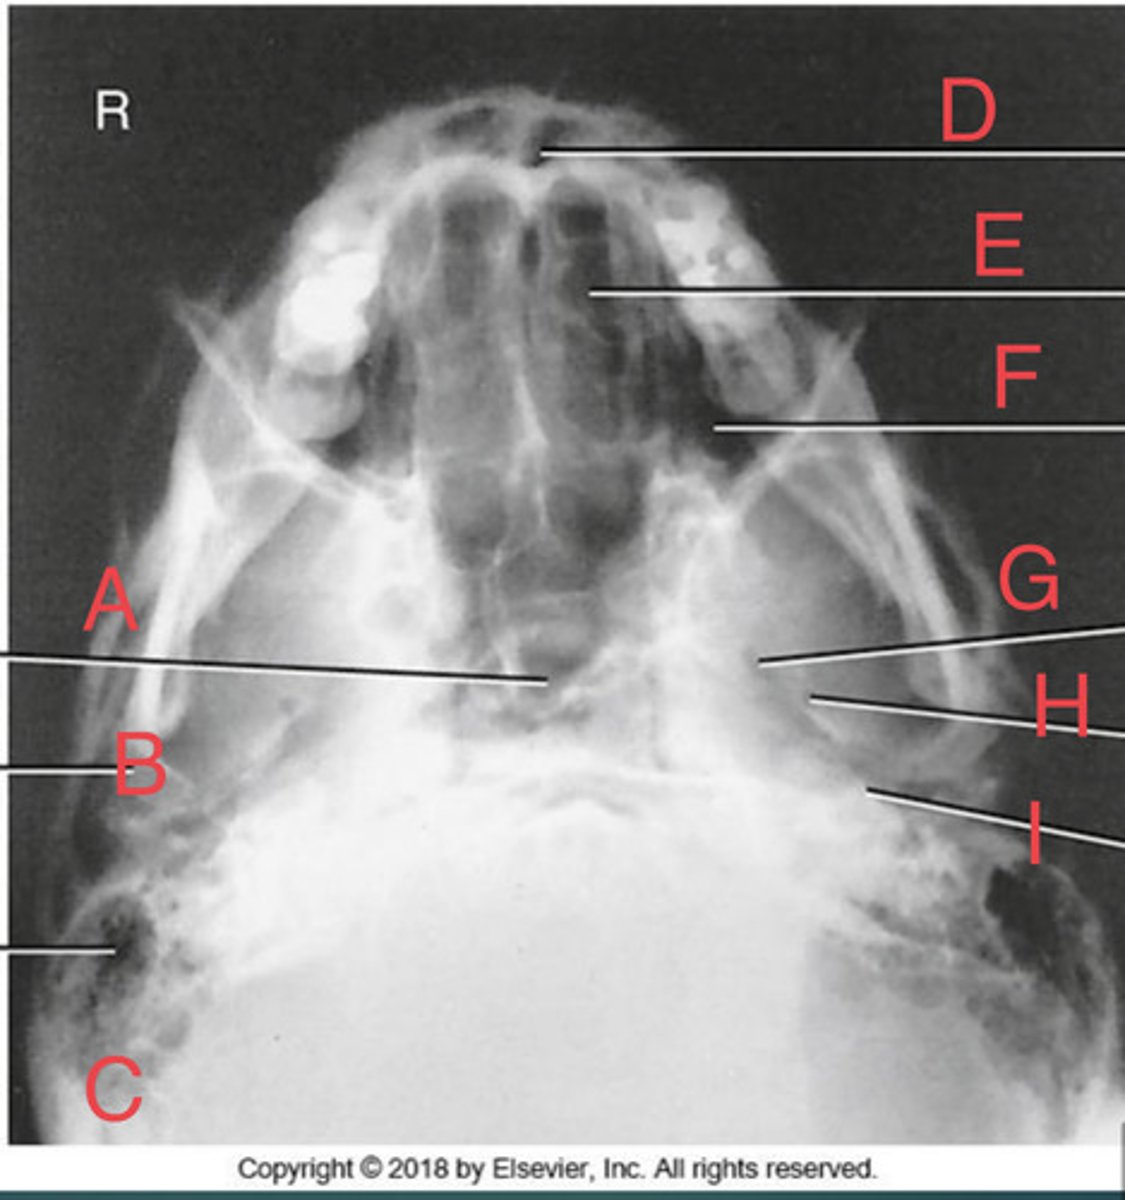

SMV sinuses

What position?

Sphenoid sinus of sphenoid bone

A.

R mandibular condyle of mandible

B.

R Mastoid air cells of temporal bone

C.

Nasal fossa

D.

L. Ethmoid sinus of ethmoid bone

E.

L maxillary sinus of maxilla

F.

L foramen ovale of sphenoid bone

G.

foramen spinosum of sphenoid bone

H.